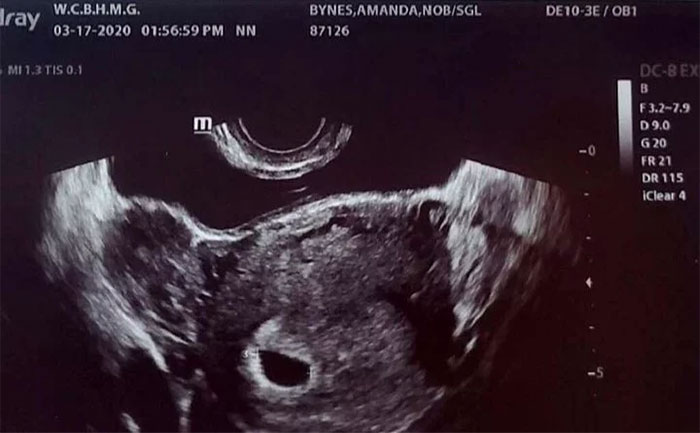

Amanda Bynes posted a photo of an ultrasound with the caption “Baby on board!” to announce her pregnancy. Her fiance also shared his excitement over the news. He posted their old selfie and the ultrasound photo with the caption, “Baby in the making,”